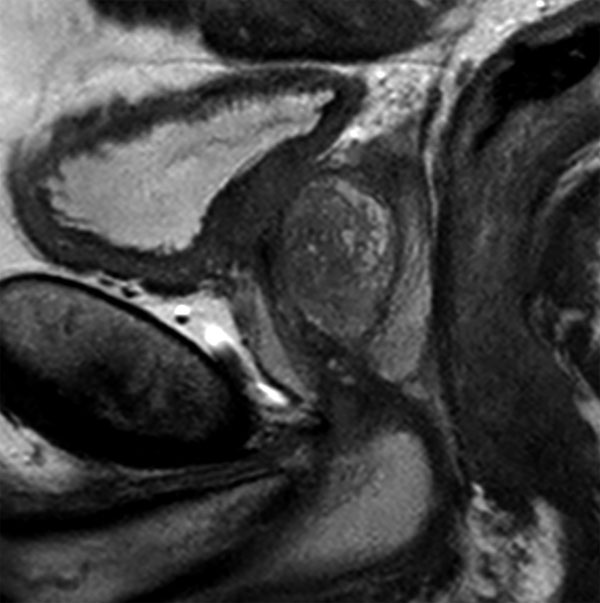

73 year old male with known prostate carcinoma. Size of 5mm, located in right posterior region. Patient is under active surveillance. Request for MR-guided prostate biopsy to re-evaluate.